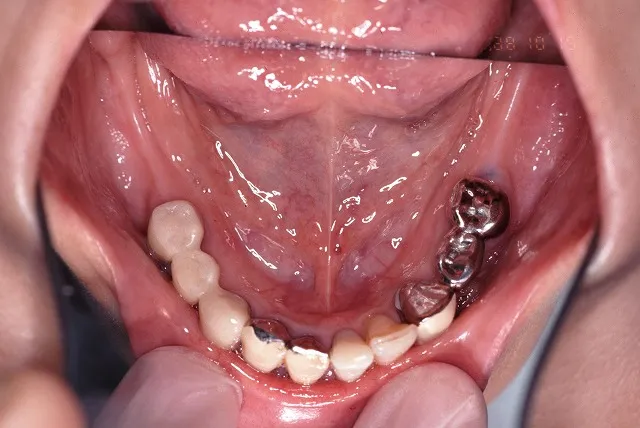

治療前

■治療前